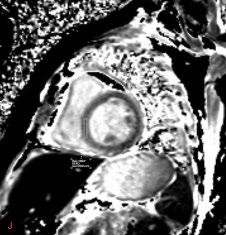

In contrast to acute complications, chronic complications are generally more unique to the Caesarean section itself, and are not typically seen with other surgical procedures, with the exception of incisional hernia. Caesarean scar niche was identified as an important cause of pain and irregular bleeding (Figure 1).

Figure 1: Caesarean scar niche.

C-section: Caesarean section; US: ultrasound.

Acute complications included injury to adjacent organs, bleeding, and haemorrhage, along with the risks associated with anaesthesia, typical of acute complications seen with most surgical procedures. The organs most at risk during a Caesarean section are the bladder, ureters, and bowel, due to their proximity to the uterus. Most of the postoperative collections observed were located anterior to the uterus in the uterovesical space, or wound infections in the subcutaneous tissue.

The complications identified in this local review of Caesarean section cases align with the recognised complications documented in the literature.

The purpose of this pictorial review is to depict the various complications associated with Caesarean sections, and their appearances on different imaging modalities using local cases.

While Caesarean sections are generally considered safe, there are a range of associated complications. With the increasing frequency of Caesarean sections, a corresponding rise in the incidence of complications can be expected. Therefore, it is important to ensure that radiologists can effectively identify the most common complications and their features across different imaging modalities.